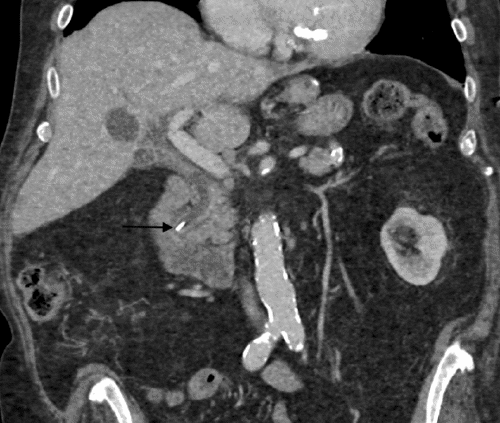

Vital signs were stable, with an obese and nontender abdomen on examination. Initial white blood count and liver function tests were normal. The computed tomography (CT) image suggested a surgical clip in the distal common bile duct (Figure 1). Magnetic retrograde cholangiopancreatography (MRCP) confirmed a surgical clip in the common bile duct surrounded by a lucent 1 cm area, suggestive of a stone. The following morning, his white count remained normal while his liver function tests became diffusely elevated (bilirubin 4.3, alkaline phosphatase 411 IU/L, aspartate aminotransferase (AST) 780 IU/L and alanine aminotransferase (ALT) 560 IU/L).

Figure 1. Coronal CT Image of Abdomen Shows Surgical Clip Migration to Distal Common Bile Duct. Published with Permission